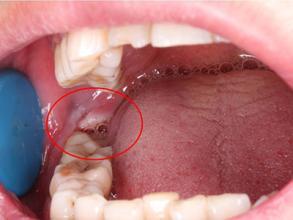

智齿发炎肿图片智齿冠周炎脓肿切开图

智齿发炎有脓包图片

尽头牙长肉包裹图片

智齿长出一半被肉包着

智齿露一半包一半图